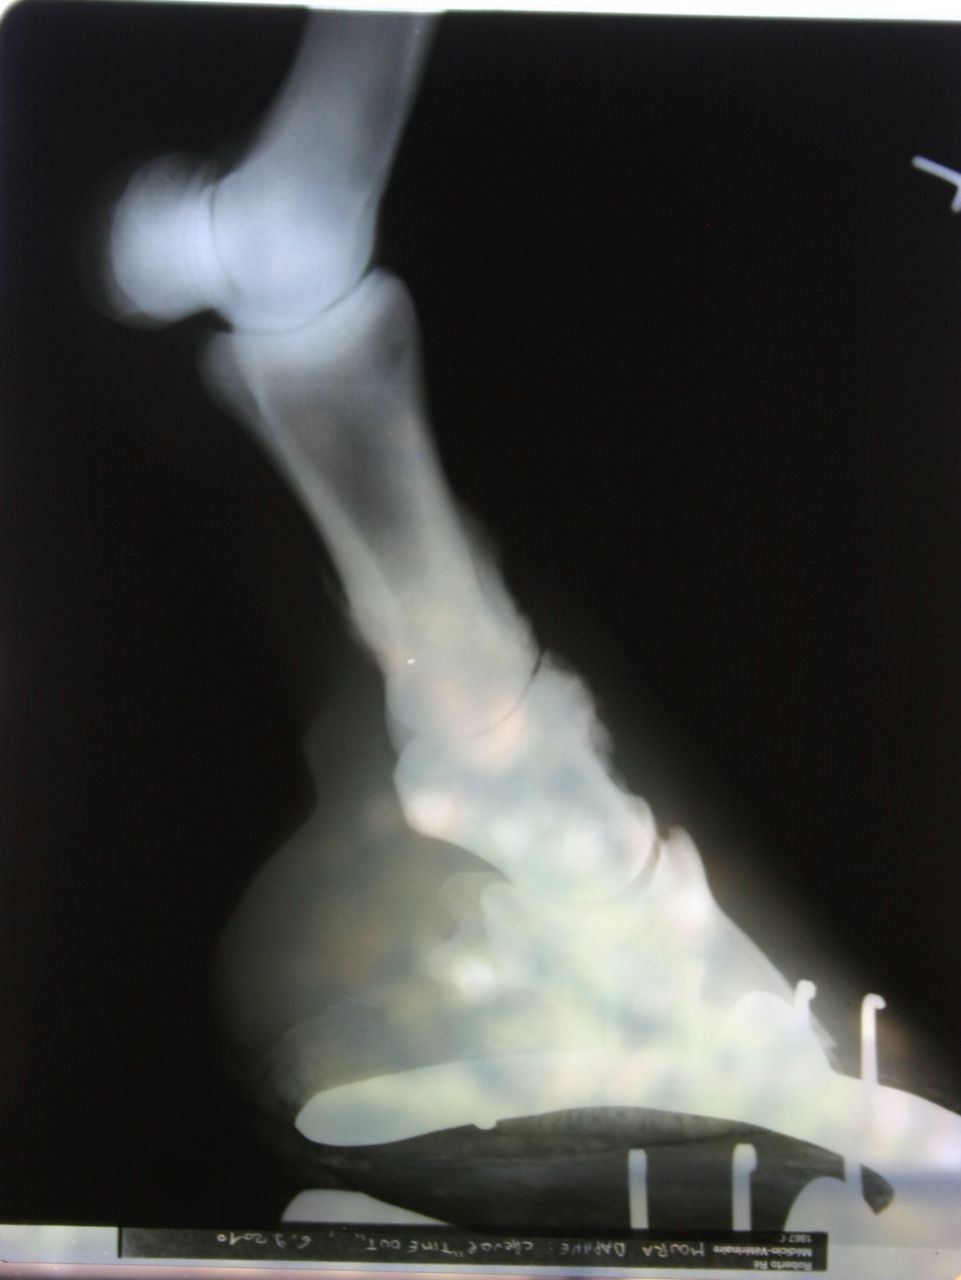

| Dire merci | pour le moment bien, mais ça fait pas longtemps qu'il est sous equipalazone en continu! et puis il avait un autre AI avant, qui était sous forme de pâte, mais j'arrive plus à me rappeler le nom, il me semble que ça finissait par "ure" j'ai fait des photos des dernières radios,s'il y en a que ça intéresse ![]() d'abord l'antérieur droit, le plus touché : on voit bien les formes aux paturons et l'articulation qui est presque entièrement soudée ![]() ![]() ![]() et puis le gauche, un peu moins grave mais bien touché quand même! ![]() ![]() |